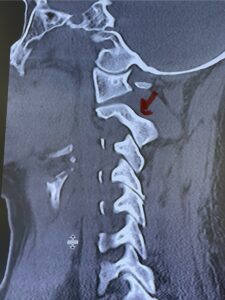

Cervical x-rays revealed a significantly increased atlanto-axial interval (Fig. 5) On review of her imaging studies it was noted that the right C2 isthmus was very thinned by the vertebral foramen (Figs 6a, b, and c) which would make an attempt at placing a C2 pars screw dangerous. A decision was made to perform an occipital-cervical fusion because only possible unilateral fixation and an extensive C1 laminectomy to be performed eliminating a fixation point if a more traditional C1-C2 was performed. Even if C1 lateral mass screws were able to be placed one could only perform a unilateral screw construct fixation to C2. We performed an occipital cervical fusion down to C4 to get enough inferior fixation and C1 laminectomy. The decompression went well. We placed a left unilateral pars screw and bilateral C3 and C4 lateral mass screws. We placed three 12 mm screws in the midline keel (Fig. 7). Postoperatively the patient had all around improvement in her symptoms and did not qualify for rehab. Her post op films at 6 weeks (Fig. 8)

Fig. 6a: Sagittal cervical CT scan demonstrating an abnormally thin right C2 isthmus prohibiting safe placement of screw (red arrow). Notice the vertebral foramen eroding the isthmus bone structure (red dot).